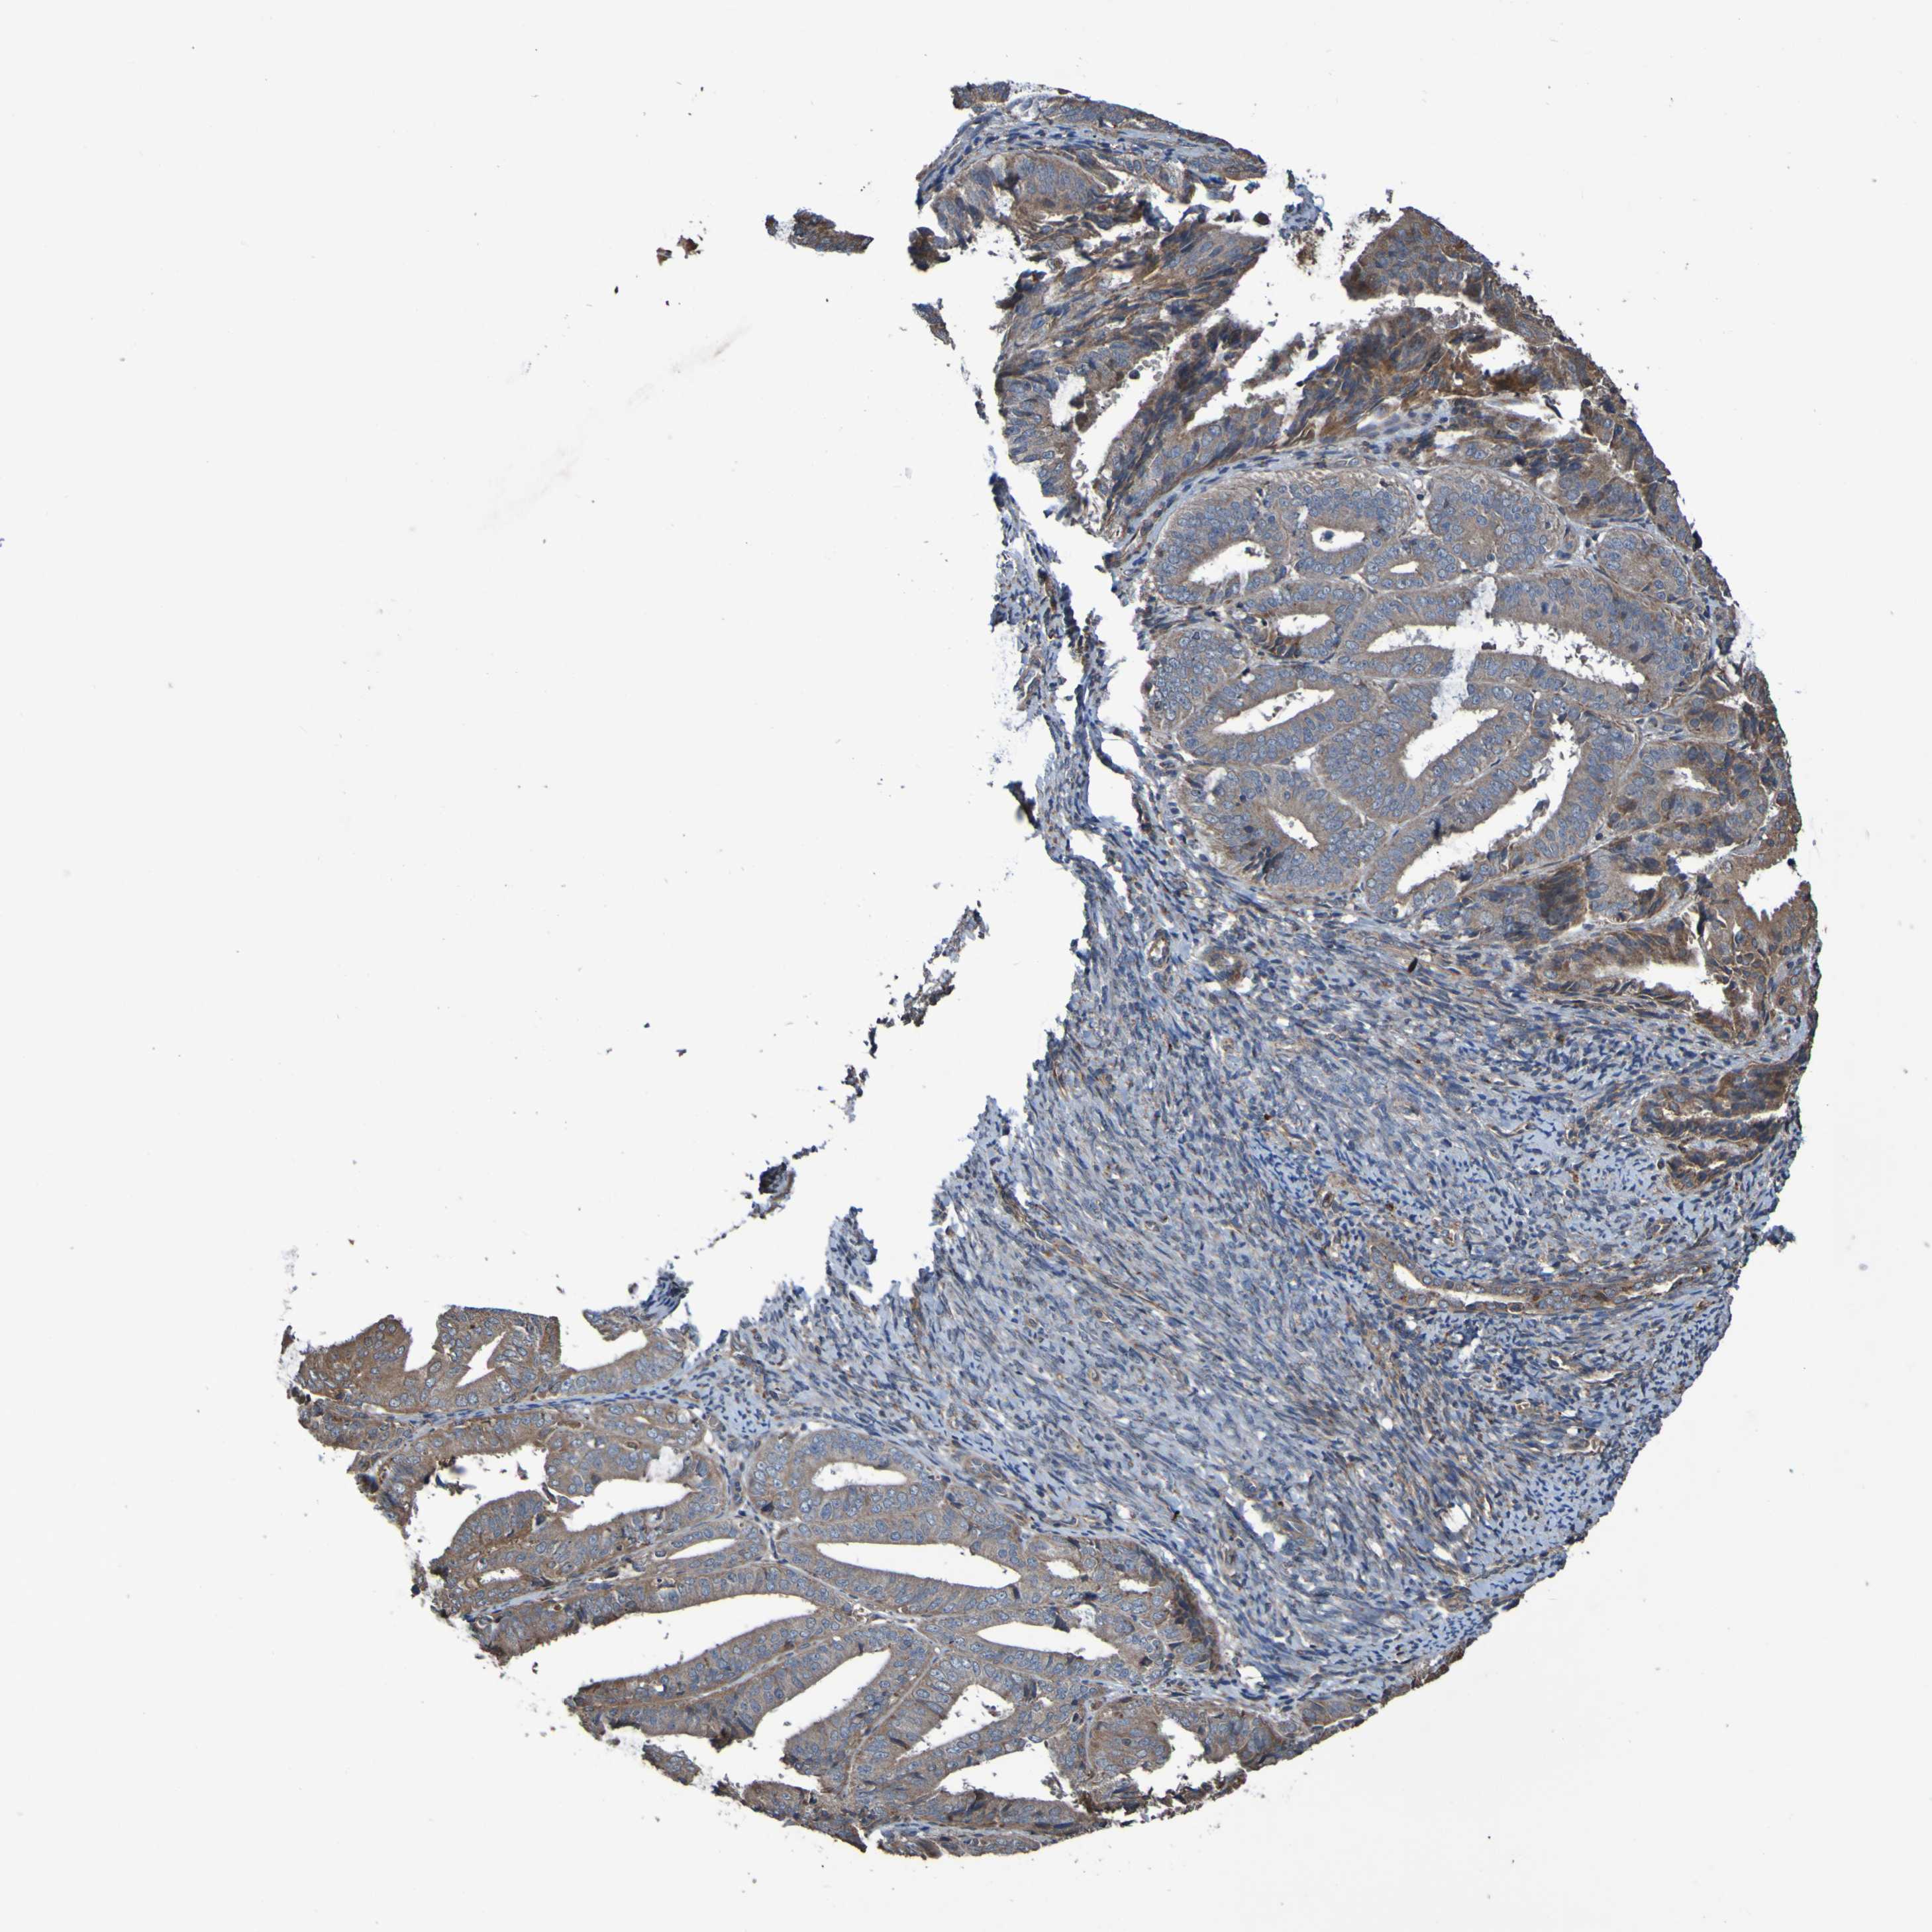

ENDOMETRIAL CANCER - Protein expressioni

A mouse-over function shows sample information and annotation data. Click on an image to view it in a full screen mode. Samples can be filtered based on level of antibody staining by selecting one or several of the following categories: high, medium, low and not detected. The assay and annotation is described here.

Note that samples used for immunohistochemistry by the Human Protein Atlas do not correspond to samples in the TCGA dataset.

Antibody stainingi

Antibody staining in the annotated cell types in the current human tissue is reported as not detected, low, medium, or high, based on conventional immunohistochemistry profiling in selected tissues. This score is based on the combination of the staining intensity and fraction of stained cells.

Each image is clickable and will lead to virtual microscopy that enables deeper exploration of all samples and also displays staining intensity scores, fraction scores and subcellular localization as well as patient and tissue information for each sample.

Antibody CAB010911

Staining

High

Medium

Low

Not detected

Intensity

Strong

Moderate

Weak

Negative

Quantity

>75%

75%-25%

<25%

None

Location

Nuclear

Cytoplasmic/membranous

Cytoplasmic/membranous,nuclear

Adenocarcinoma, NOS